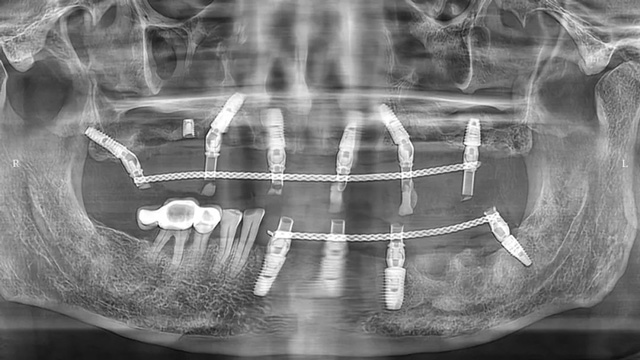

兩周后吳叔叔回院拆線,完成了下牙的多顆種植治療。別看下面的種植數量少,難度卻并不低。據余國慶醫生介紹,有一顆種植體采用的是傾斜植入,因為之前的種植體周圍有感染,拆除種植體后只能在旁邊一個極其有限的范圍內種植,種植窩洞的位置需要非常精準,很考驗醫生的技術和經驗。

下頜即刻種植后全景片